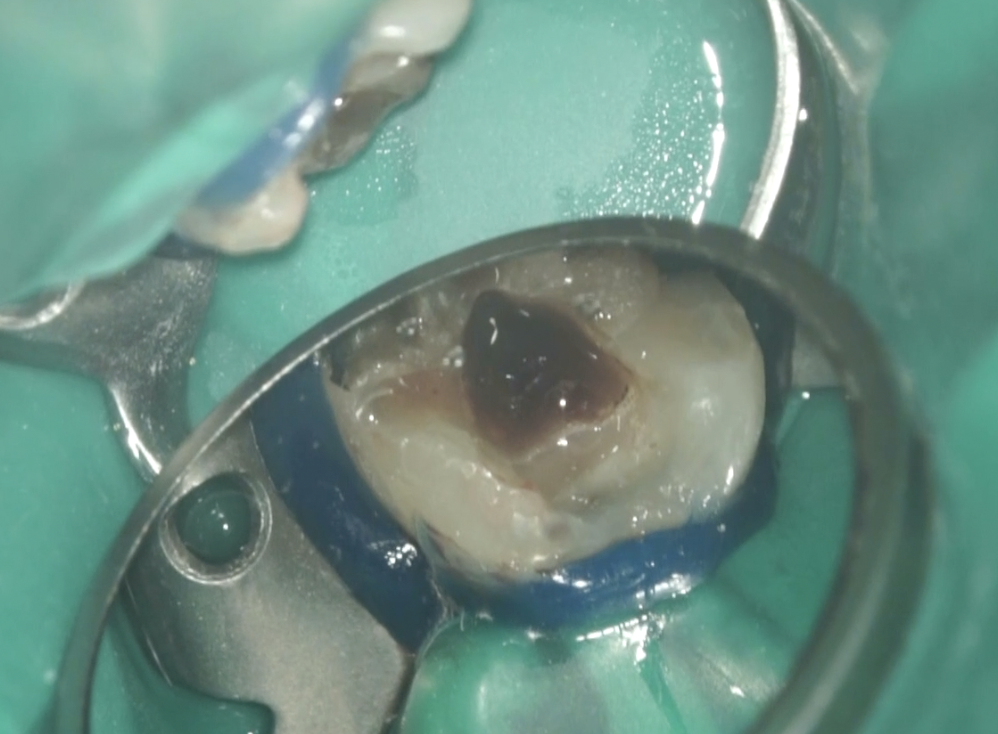

以下のように根管形成した。

Dは#60.02で形成しても出血がペーパーポイントに見られたためにProTaper Gold F5まで形成した。

ML,MBは合流していることが多いと言う解剖学的情報をもとに以下のように合流部分をチェックした。

問題はないだろう。